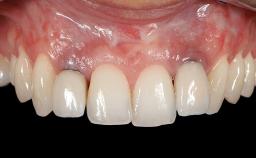

This case demonstrates that a connective-tissue graft in combination with a coronally positioned graft is an effective method of treating cases with peri-implant mucositis and an abutment-level sinus abscess. A 42-year-old man presented with a swelling adjacent to an implant crown at site 21. The swelling had been present for approximately three weeks and was constrained to the buccal and palatal gingival aspects of the implant. A discharge was noted on finger pressure, with localized gingival recession present on the mid- and distolabial aspects of the crown.